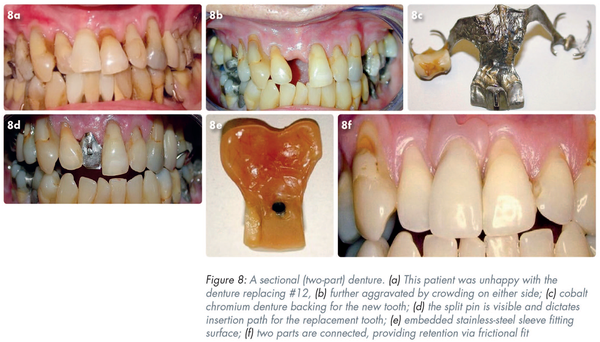

The patient in Figure 8a is dissatisfied with the appearance of her denture replacing #12. The space is constricted by the crowding caused by #13 and #11 (Figure 8b).

The cobalt chromium denture (Part 1) (Figure 8c) is the backing to the new tooth. In Figure 8d the split pin (two half-round sections of wiptam wire soldered to the framework) is visible.

This pin will dictate the path of insertion of the replacement tooth (Part 2). The fitting surface of Part 2 (Figure 8e) shows an embedded stainless-steel sleeve. In Figure 8f the two parts have been connected and are providing excellent retention by virtue of their frictional fit. The horizontal path of insertion of the tooth (Part 2) has eliminated the possibility of a “black triangle” and has allowed suitable gingival architecture.